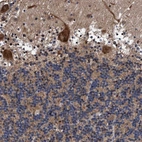

Immunohistochemical staining of human cerebral cortex shows strong nuclear positivity in neurons.